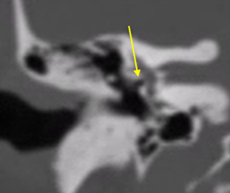

f1.png  f2.png  f3.png

Tomografía tridimensional 1perforacion tabla externa del seno frontal  Figura 1. Tomografía contrastada con ocupación de los senos frontal y etmoidal, además de formación de absceso en región frontal. Figura 2. Tomografía computarizada con opacificación de seno maxilar izquierdo y etmoidal izquierdo anterior.